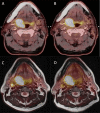

Reproducibility of (18)F-FDG PET uptake measurements in head and neck squamous cell carcinoma on both PET/CT and PET/MR

Objective: To investigate reproducibility of fluorine-18 fludeoxyglucose ((18)F-FDG) uptake on (18)F-FDG positron emission tomography (PET)/CT and (18)F-FDG PET/MR scans in patients with head and neck squamous cell carcinoma (HNSCC).

Methods: 30 patients with HNSCC were included in this prospective study. The patients were scanned twice before radiotherapy treatment with both PET/CT and PET/MR. Patients were scanned on the same scanners, 3 days apart and according to the same protocol. Metabolic tumour activity was measured by the maximum and peak standardized uptake value (SUVmax and SUVpeak, respectively), and total lesion glycolysis from the metabolic tumour volume defined from ≥50% SUVmax. Bland-Altman analysis with limits of agreement, coefficient of variation (CV) from the two modalities were performed in order to test the reproducibility. Furthermore, CVs from SUVmax and SUVpeak were compared. The area under the curve from cumulative SUV-volume histograms were measured and tested for reproducibility of the distribution of (18)F-FDG uptake.

Results: 24 patients had two pre-treatment PET/CT scans and 21 patients had two pre-treatment PET/MR scans available for further analyses. Mean difference for SUVmax, peak and mean was approximately 4% for PET/CT and 3% for PET/MR, with 95% limits of agreement less than ±20%. CV was small (5-7%) for both modalities. There was no significant difference in CVs between PET/CT and PET/MR (p = 0.31). SUVmax was not more reproducible than SUVpeak (p = 0.09).

Conclusion: (18)F-FDG uptake in PET/CT and PET/MR is highly reproducible and we found no difference in reproducibility between PET/CT and PET/MR.